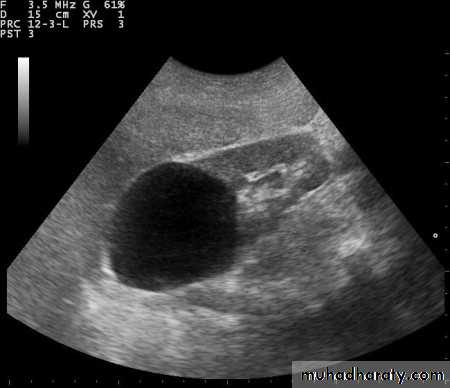

Congenital intrinsic pelviureteric junction (PUJ) obstruction

In this disorder, peristalsis is not transmitted across the pelviureteric junction.Childern and young adult

Dilatation of the pelvis and calices, with an abrupt change in caliber at the pelviureteric junction

the ureter is either narrow or normal in size.